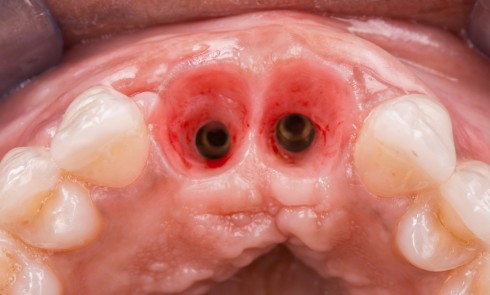

L’implant

- Site 23

- Mis en place il y a 12 ans